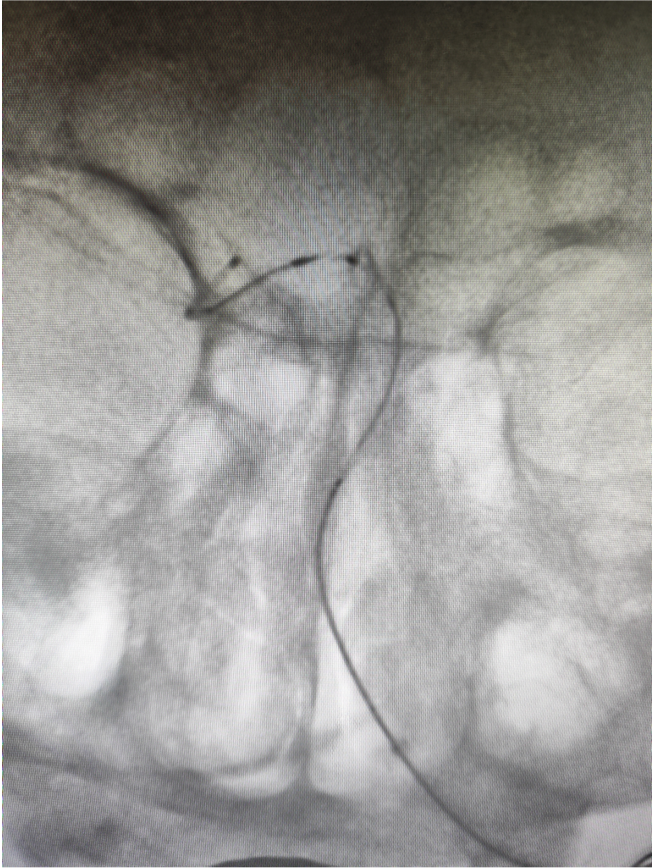

微导丝超选至右侧大脑后动脉,微导管通过狭窄段困难。考虑原位狭窄,行球囊扩张。

球扩后狭窄改善后不能维持,沿微导丝微导管通过狭窄段至右侧大脑后动脉,释放Enterprise2支架一枚。

Locaste长鞘头端柔软,近端支撑力强。Skathi远端通路导管支撑力足够,系统稳定,操作顺畅,通过性好,远端亲水头手感丝滑,裸奔直接通过V3-4段,到达基底动脉狭窄近段轻松自如。狭窄部位狭窄程度较重,通过困难,逐步球扩后置入支架,Skathi远端通路导管极其稳定,通过球囊、支架系统顺利,可为进一步的安全治疗奠定基础。